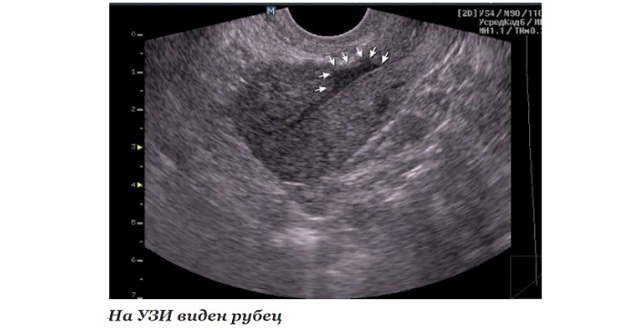

- ЭхоКГ или УЗИ сердца помогает установить наличие локализованных или диффузных участков соединительной ткани, позволяет уточнить местонахождение и степень распространения;